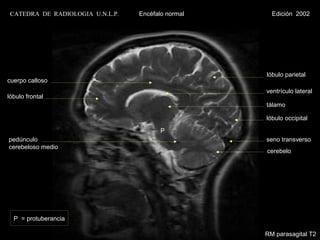

CATEDRA DE RADIOLOGIA U.N.L.P.   Encéfalo normal     Edición 2002

lóbulo parietal

cuerpo calloso

ventrículo lateral

lóbulo frontal

tálamo

lóbulo occipital

P

pedúnculo                                           seno transverso

cerebeloso medio

cerebelo

P = protuberancia

RM parasagital T2